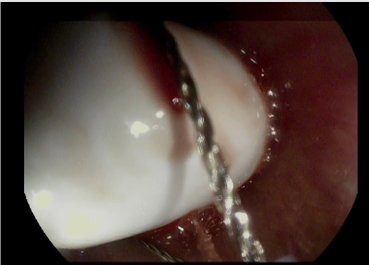

The patient swallowed the capsule (Pillcam SB3, Medtronic) smoothly without real-time monitoring. The capsule recording was examinated on the following day, and showed persistent esophageal mucosa images, so it was suspected to be stuck in a Zenker diverticulum. The patient was asymptomatic, but he was unable to report capsule excretion. A neck radiograph was performed, showing a radiopaque foreign body, compatible with the capsule, retained in the patient’s neck. Due to the risk of a spontaneous expulsion of the capsule in the upper airways, it was decided to remove it. The patient underwent upper endoscopy, and the capsule was extracted after several efforts (Figures 1 & 2). On the subsequent days the patient had an uneventful course and was discharged in stable clinical conditions.